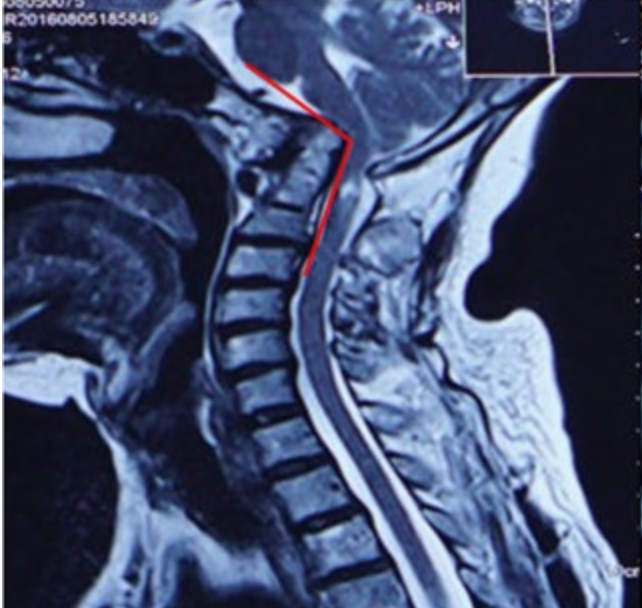

MRI

Cervico-medullary angle < 135 degrees

- the line parallel to ventral side of medulla oblongata

- the line parallel to the ventral side of the upper cervical cord

- normal angle is 135-175°

- <135° consistent with vertical settling and correlated with myelopathy

From: Guo et al Sci Rep 2019. http://creativecommons.org/licenses/by/4.0/.